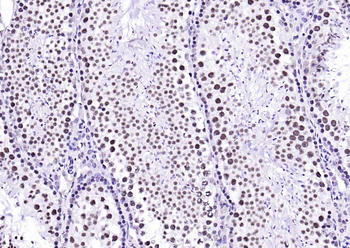

IHC staining of FFPE human brain with Ubiquitin antibody (clone PBQN-1). Required HIER: boil tissue sections in pH9 10mM Tris with 1mM EDTA for 10-20 min followed by cooling at RT for 20 min.